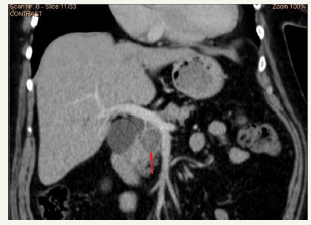

Figure 5A & 5B :MRCP view of cystic enlarged pancreatic duct in the head of the pancreas (red arrows) and moderate enlargement in the body (green arrows) and enlarged common bile duct due to compression in the terminal part (yellow arrows).